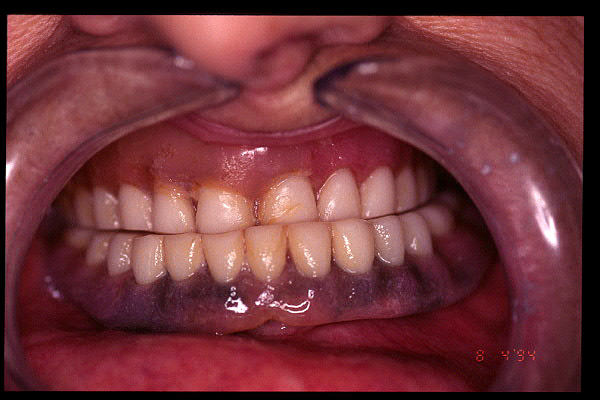

CM Caries y enfermedad periodontal avanzada